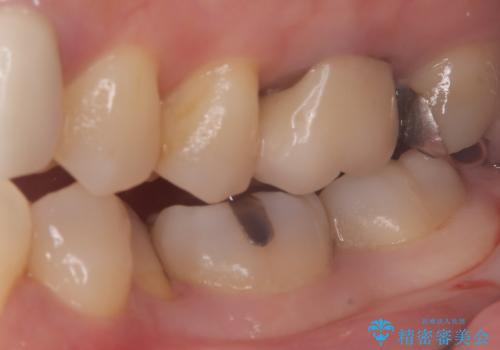

- 主訴:口を開けると所々入っている銀の詰め物が目立つので白い物にやり替えたい。

下顎大臼歯部に入っている保険適用のメタルインレーを、適合性と審美性の良いセラミックインレーでのやり替えとなりました。

メタルインレーを除去した際、古い裏層材やカリエスは除去し新たにCR裏層しています。

セラミックインレーセット時はラバーダム防湿を行っています。